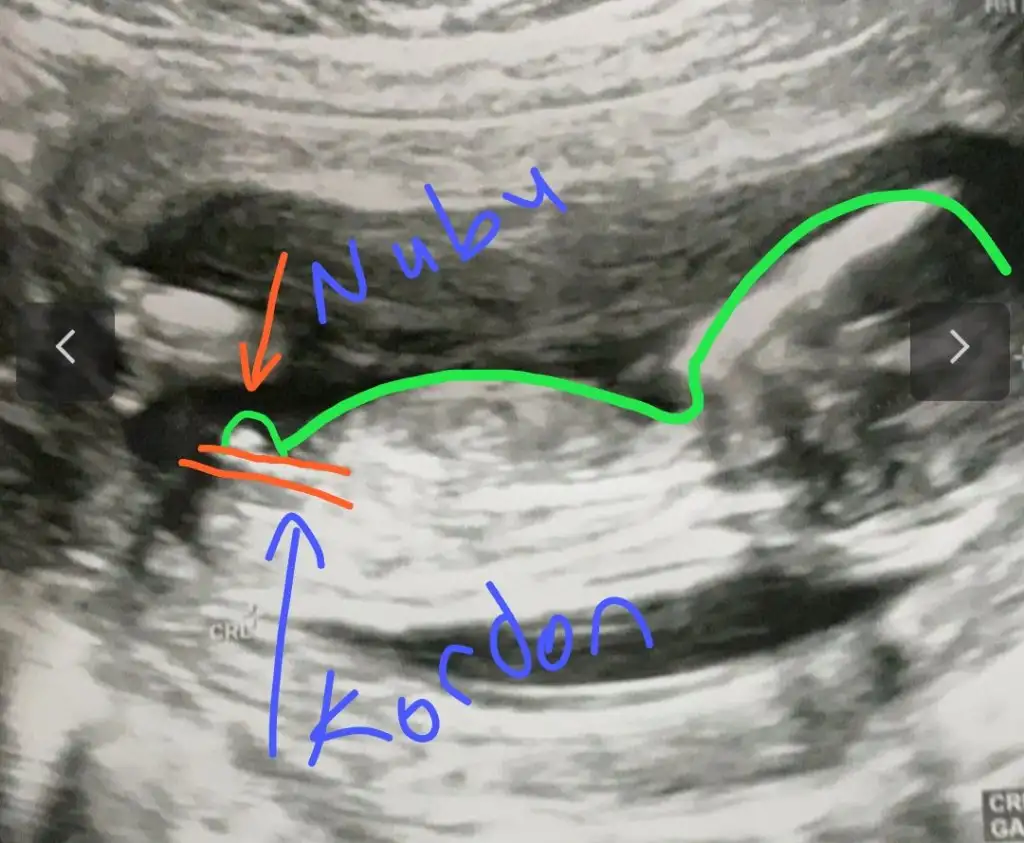

dr soylemeden siz gorun genital nub teorisi ( bebegin cinsiyeti)

Ikra meyra Ikra meyra canım selam başka bir doktor bugün erkeğe benziyor dedi nub görüntüsü vermedi ama kalca ölçümü buydu sence nedir

Ben anlamadım bunu canım 11 12 13 haftalar paylaşın tekrar bakıp çizim ☺️ yada varsa başka USG paylaşın

Canım bu 12 artı 4 dü burda doktor kıza benziyor yüzde 80 demişti